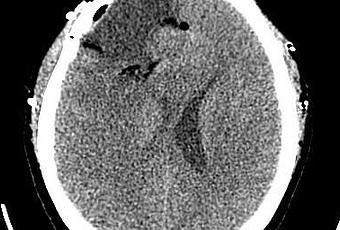

Corte axial post quirúrgico, adecuada resección de lesión. Axial CT scan, showing a proper tumor resection

Corte axial post quirúrgico, adecuada resección de lesión.